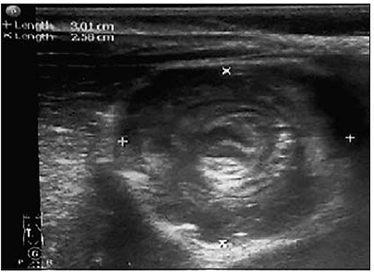

Figure 3. Intussusception sonographic view – target sign (examination and image made by K. Soldatenkova) | Figure 4. Mesenterial lymphadenitis sonographic view (examination and image made by K. Soldatenkova) |

Main diagnostic methods used at Children’s Clinical University Hospital were abdominal sonography and plain abdominal X-ray. Computer tomography for intussusception confirmation was used only once in a 10-year period. Abdominal sonography was made in 81.1 % (120) patients with sensitivity of 95.8 % (Figure 3). Possible pathologic lead point was found in 41.7 % (50) of cases (Figure 4). In recent years sonography use in control for early recurrence has increased, made in 55 (37.2 %) patients, revealed 12 (8.1 %) recurrence cases. Plain abdominal X-ray was made in 66.9 % (99) patients, ileus signs were found in 58.6 % (58), irregular distribution of gases in 29.3 % (29) and normal – in 12.1 % (12) cases.

Sonography has become the diagnostic standard for confirmation of suspected intussusception, with high sensitivity (98–100 %) and specificity (88–100 %), [5, 139; 12, 59; 14, 519] especially in ileocolic intussusception form [2]. In our study abdominal sonography was performed in 81.1 % of patients, with sensitivity of 95.8 %. Abdominal radiography is the second diagnostic method used in the study – 99 cases (66.9 %), no cases of perforation detected. Tareen et al. analysed a 15-year experience in necessity of abdominal radiography (AR) in children with intussusception. They concluded that AR should always be performed when clinical peritonitis is present, but is not otherwise necessary in children with suspected or confirmed intussusception [13, 90].